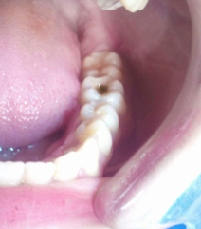

The purpose of the present study was to compare the clinical performance of bulk-fill composite resin with that of layered composite resin restorations in occlusal class I cavity of permanent molar teeth. This study includes a total of 104 teeth having class I cavity of 3-4 mm depth in the occlusal surface. They were restored either with layered composite resin or bulk-fill composite resin of 52 teeth in each group. To observe the retention, marginal adaptation and color match, all restorations were assessed by using modified United States Public Health Services (USPHS) and Ryge’s criteria at baseline, 3, 6 and 12 months. The results of 12 months observation showed that retention of 38 layered composite and 48 bulk-fill composite resin restorations revealed alpha rating, which was statistically significant. The marginal adaptation of 37 layered composite resin and 47 bulk-fill composite resin restorations also demonstrated alpha rating and the differences between two groups were statistically significant. However, there were no significant differences between the layered composite resin and bulk-fill composite resin restorations in respect to color match. It can be concluded that bulk-fill composite resin showed better clinical outcome than that of layered composite resin in the restorations of occlusal class I cavity.